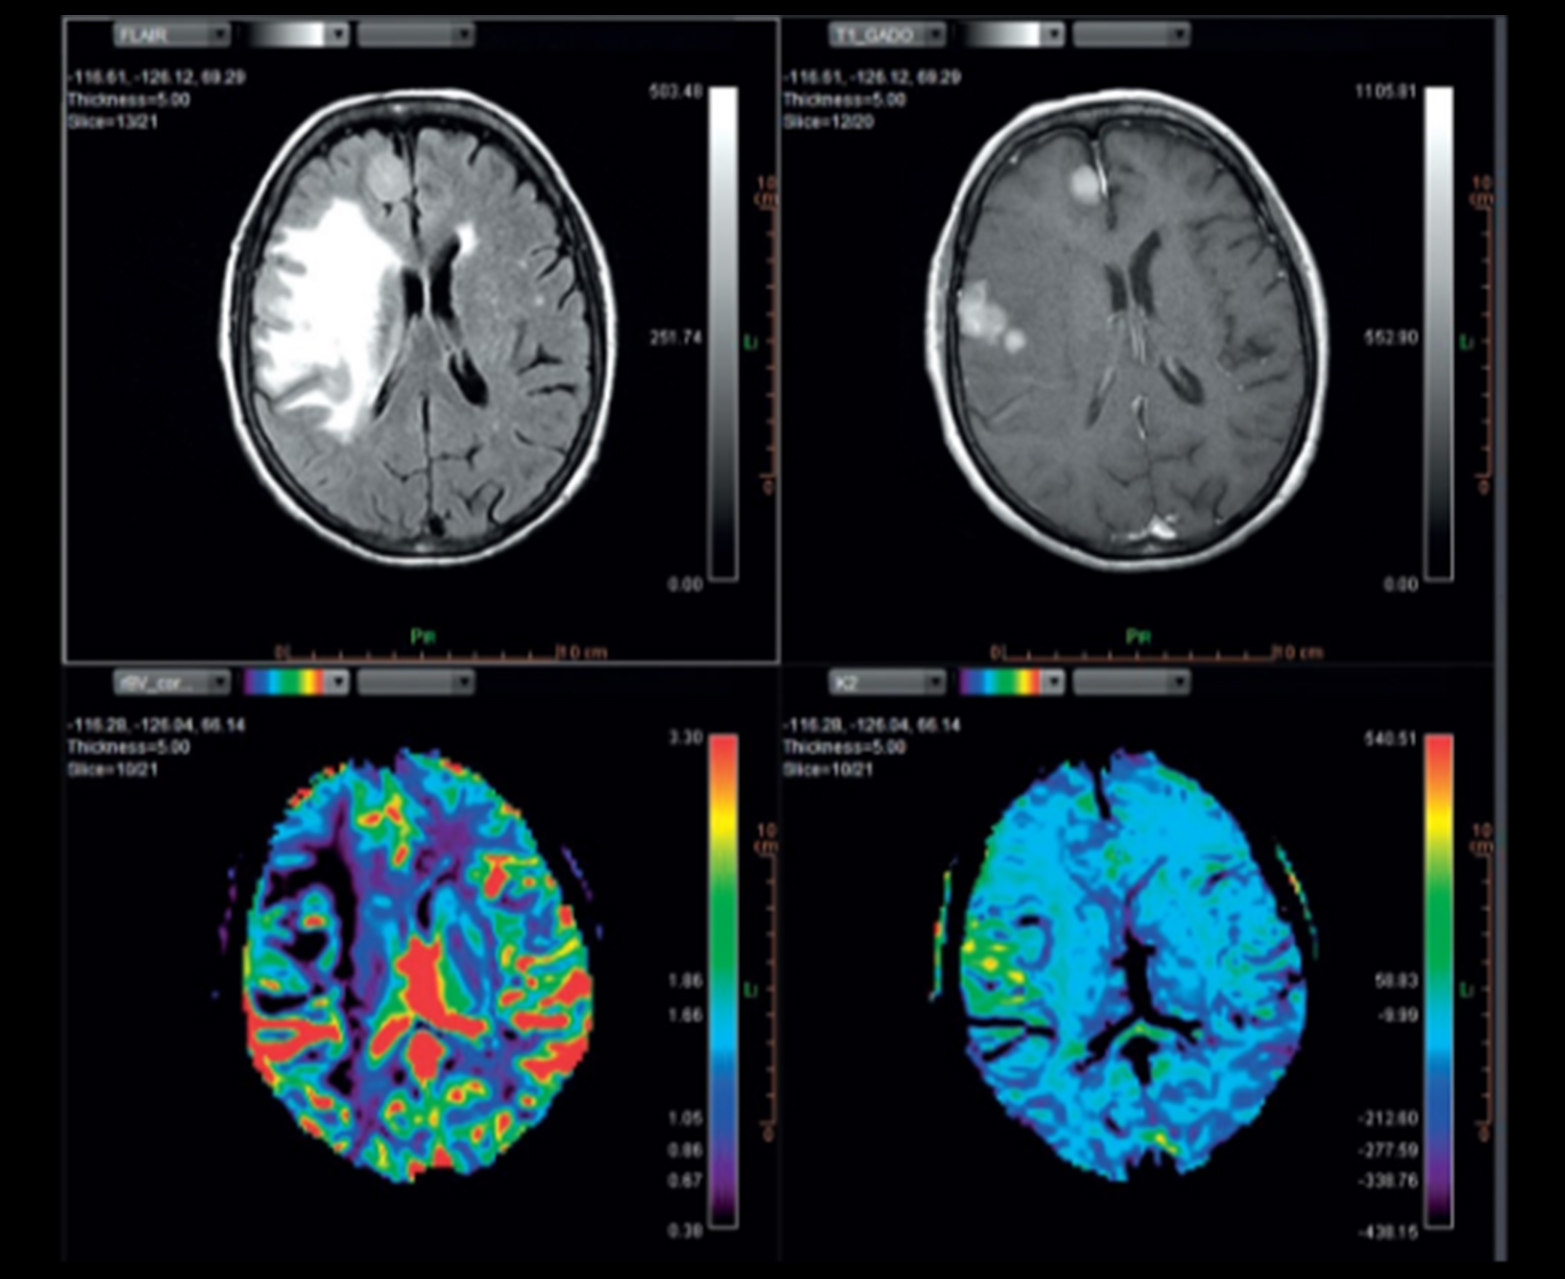

Неврология

Оптимизированное решение для диагностической помощи при нейровизуализации взрослых и детей

Автоматически и точно рассчитывает качественные и количественные карты проницаемости.

• Обнаружение, классификация и характеристика опухолей с быстрым доступом к качественной и количественной информации индивидуальный макет

Многопараметрическое настраиваемое отображение карт диффузии и перфузии, включая карты rCBV_corrected и K2

Голова и шея Количественные карты проницаемости

Количественные карты проницаемости головы и шеи